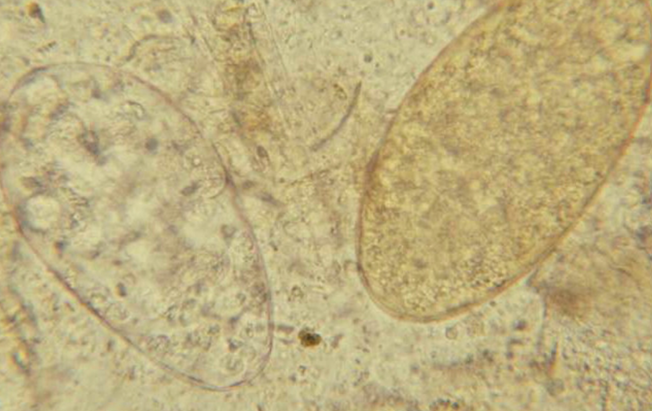

Œufs de Trématodes : à droite Fasciola et à gauche Paramphistome (on peux les distinguer uniquement par la couleur)